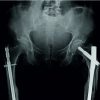

Recognizing the bilateral AFFs and the imminent risk of a right-sided fracture, prophylactic intramedullary nailing was performed on the right femur (Fig. 3), based on the current clinical evidence. This approach also facilitated positioning for subsequent fracture reduction and reconstruction nailing of the left femur (Fig. 4), conducted 2 days later. The postoperative course was uneventful. Bisphosphonate therapy was discontinued, and the patient was started on teriparatide injections, calcium, and vitamin D supplementation. After satisfactory post-operative X-rays (Fig. 5), full weight-bearing mobilization with walker support was initiated.

Six weeks into rehabilitation, during one of the mobilization sessions, the patient reported pain at the site of prophylactic nailing in the right femur. Radiographs revealed a minimally displaced fracture in the proximal third of the right femur (Fig. 6). Conservative management was pursued due to the absence of significant displacement or angulation, which was probably due to the prophylactic nail in situ. Mobilization was restricted to bedside exercises for 6 weeks, followed by a gradual return to full weight-bearing activity. There was no complaint of worsening of pain or any other symptoms with this conservative approach. With regular clinical and radiological follow-ups, the patient demonstrated progressive healing, transitioning to single crutch-assisted ambulation by 6 months. One-year post-surgery, complete bilateral fracture consolidation was observed (Fig. 7), and the patient achieved unaided, pain-free mobility. She is still under follow-up and is doing well, with no further symptoms so far.